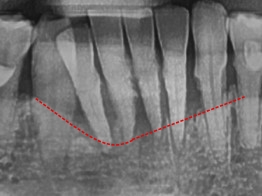

사진에서도 빨간선까지가 정상 잇몸뼈의 높이라면

위 환자분의 뼈는 이미 치주염으로 인해 파란선까지 내려앉은 걸 확인할 수 있었고

그 틈으로 음식물, 치태가 쌓이며 피도 나고 잘 붓습니다.